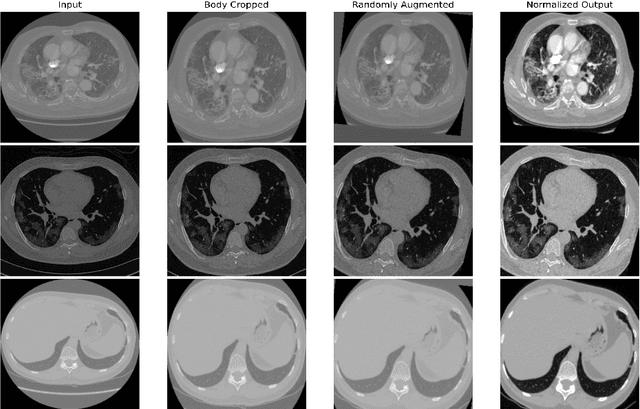

Abstract:Quantitative lung measures derived from computed tomography (CT) have been demonstrated to improve prognostication in coronavirus disease (COVID-19) patients, but are not part of the clinical routine since required manual segmentation of lung lesions is prohibitively time-consuming. We propose a new fully automated deep learning framework for rapid quantification and differentiation between lung lesions in COVID-19 pneumonia from both contrast and non-contrast CT images using convolutional Long Short-Term Memory (ConvLSTM) networks. Utilizing the expert annotations, model training was performed 5 times with separate hold-out sets using 5-fold cross-validation to segment ground-glass opacity and high opacity (including consolidation and pleural effusion). The performance of the method was evaluated on CT data sets from 197 patients with positive reverse transcription polymerase chain reaction test result for SARS-CoV-2. Strong agreement between expert manual and automatic segmentation was obtained for lung lesions with a Dice score coefficient of 0.876 $\pm$ 0.005; excellent correlations of 0.978 and 0.981 for ground-glass opacity and high opacity volumes. In the external validation set of 67 patients, there was dice score coefficient of 0.767 $\pm$ 0.009 as well as excellent correlations of 0.989 and 0.996 for ground-glass opacity and high opacity volumes. Computations for a CT scan comprising 120 slices were performed under 2 seconds on a personal computer equipped with NVIDIA Titan RTX graphics processing unit. Therefore, our deep learning-based method allows rapid fully-automated quantitative measurement of pneumonia burden from CT and may generate results with an accuracy similar to the expert readers.